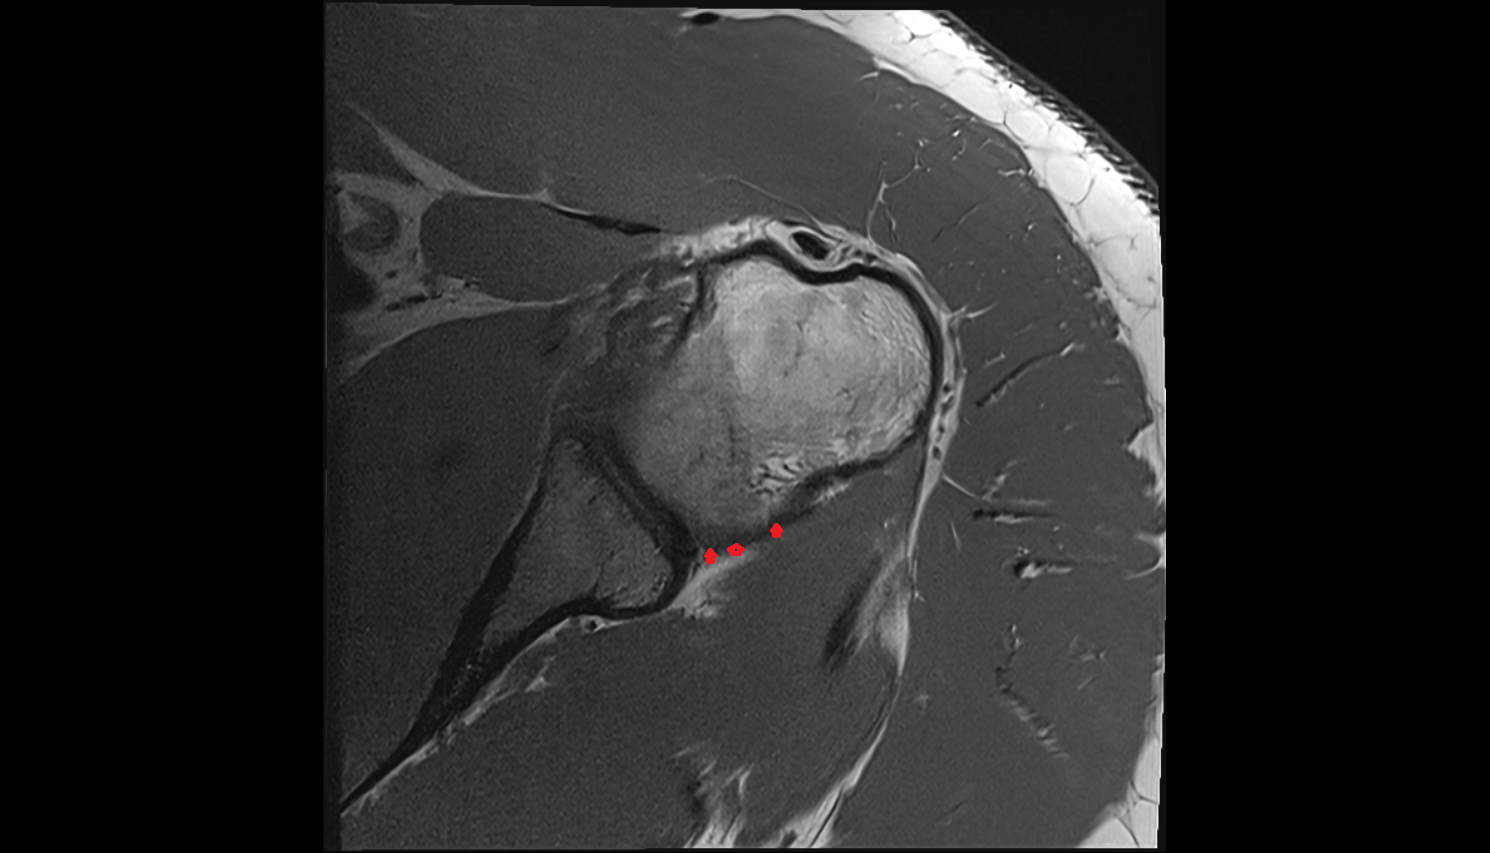

- Glenoid labrum

- Shoulder joint (glenohumeral joint)

- Glenohumeral joint capsule

- Supraspinatus tendon

- Infraspinatus tendon

- Subscapularis tendon